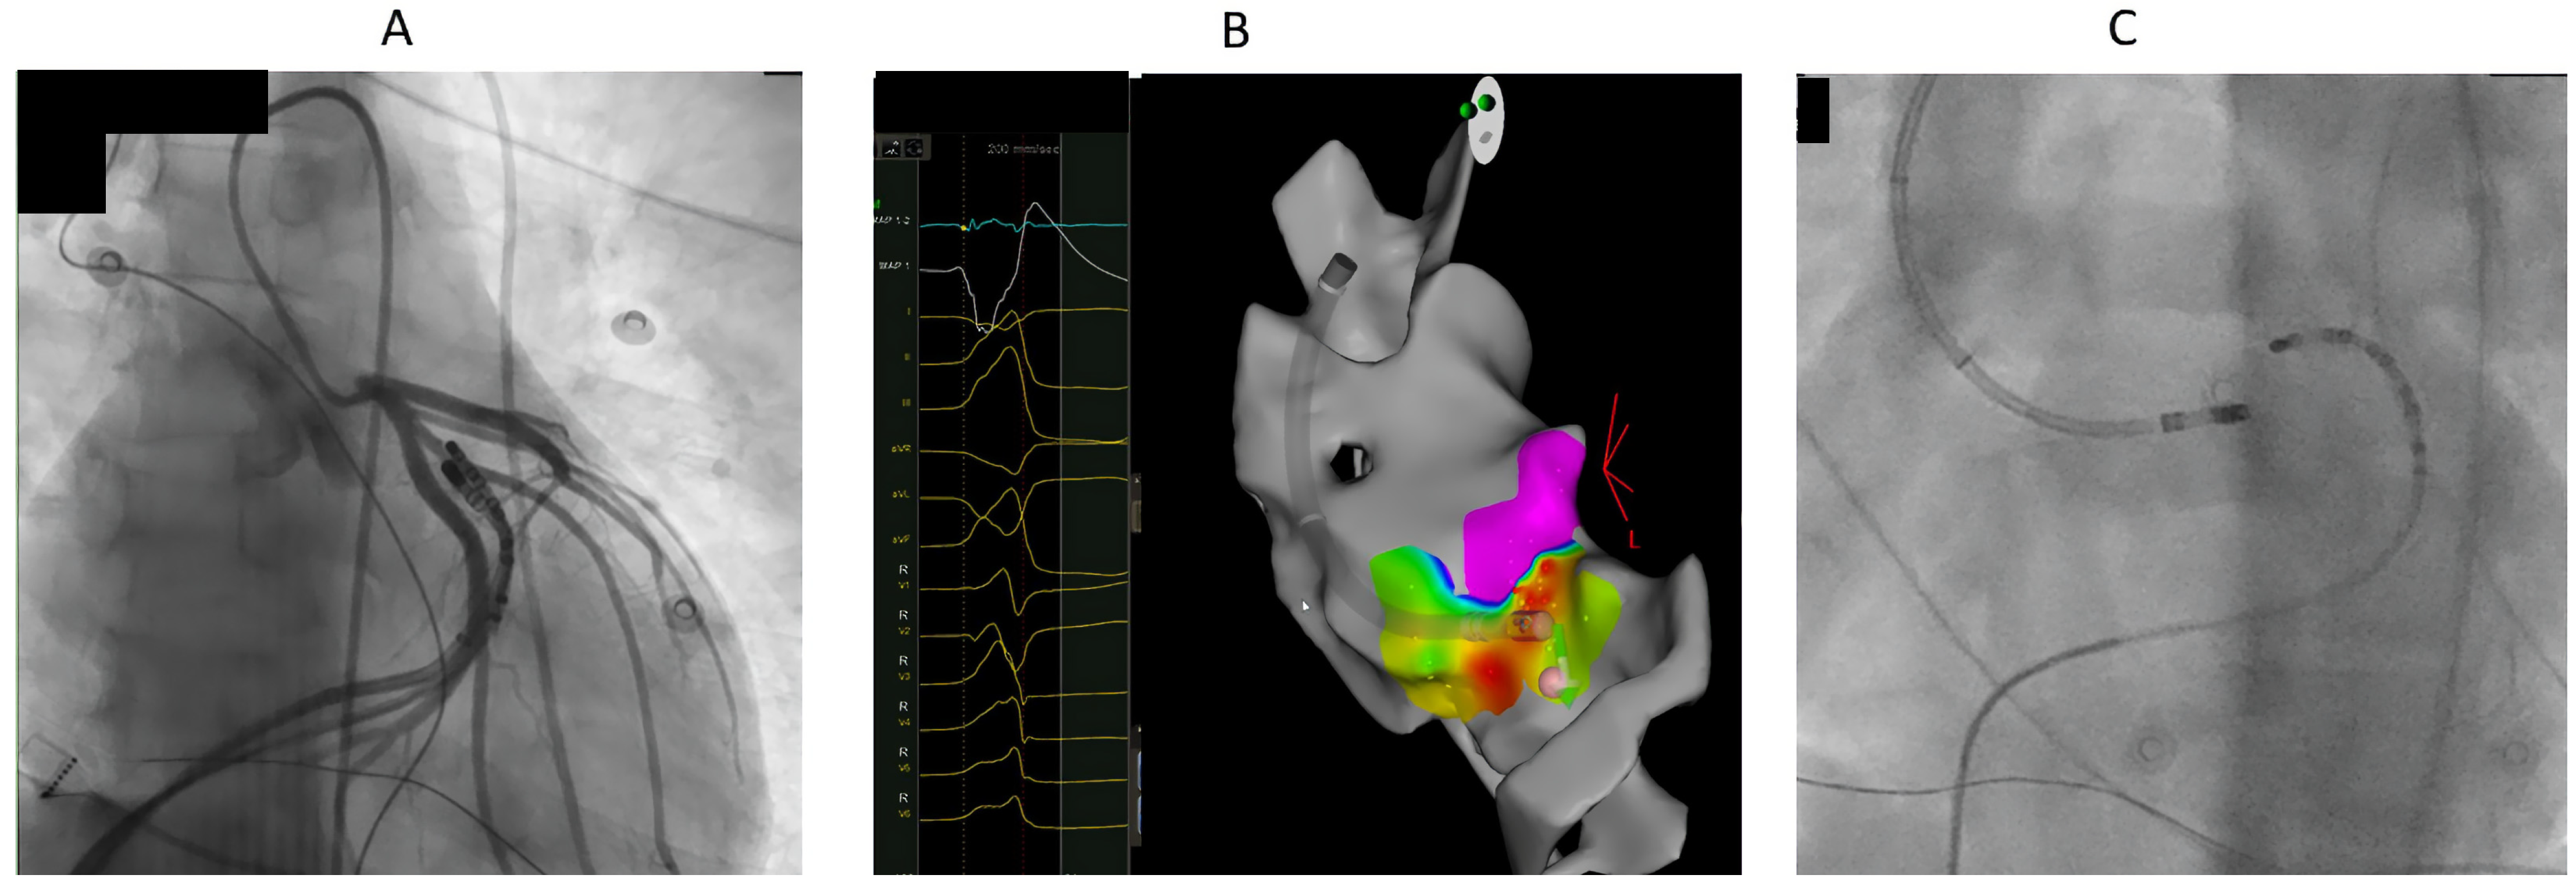

7.1. Procedure

8.2. Ablation Sites